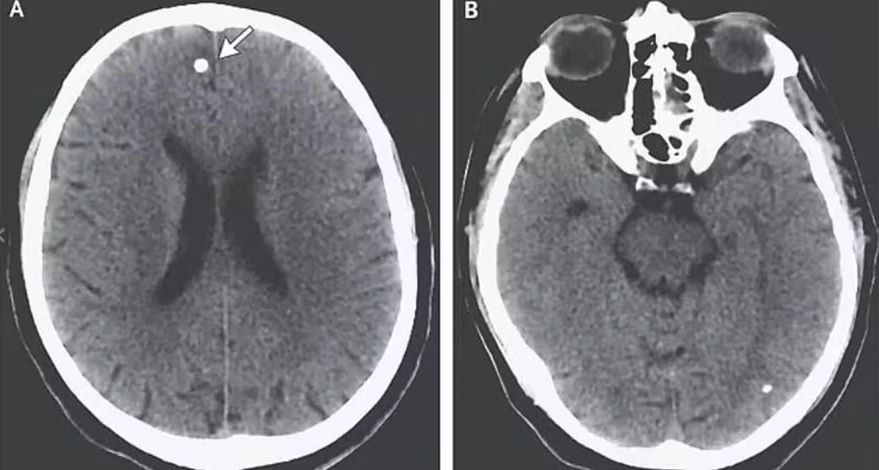

Novos exames detectaram lesões no cérebro e a presença de duas espécies de parasita: Taenia saginata, associada a carne bovina, e Taenia solium, que pode ser transmitida por carne suína ou vegetais contaminados. A Taenia solium é capaz de liberar ovos que se disseminam pelo corpo, afetando músculos, cérebro e outras partes.

De acordo com a médica infectologista Liz Ligia Pierrotti, os ovos eclodem, as larvas invadem o intestino e caem na corrente sanguínea, podendo se alojar no sistema nervoso central, nos músculos, olhos ou coração, entre outras regiões.

T.E. foi tratada com esteroides e medicamentos antiparasitários, permanecendo internada por três semanas até a eliminação completa dos ovos do cérebro. Seis meses depois, já não apresentava sintomas, mas seu caso serve como um alerta contra essa prática perigosa.